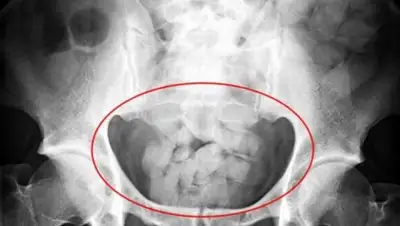

Казахстанец перевозил в желудке два прозрачных полимерных свертка с порошкообразным веществом.  Экспертиза установила, что это вещество - героин, общий вес которого составил 77 гр., что относится к особо крупным размерам.